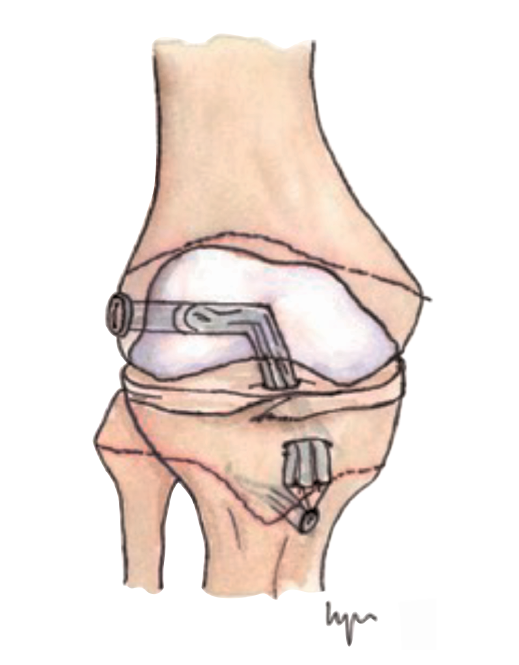

Figura 4. Técnica transepifisaria o todo epifisaria.

Otra de las técnicas de ahorro fisario es la llamada all epiphyseal. La primera de estas técnicas fue descrita por Anderson(13)(Figura 4) y está indicada en pacientes en estadio de Tanner I, II o III. Se realiza evitando la invasión de la fisis por parte de los túneles, utilizando injerto cuadrifascicular de isquiotibiales, que son estabilizados en el fémur mediante un sistema de tenosuspensión cortical y en la tibia con un tornillo interferencial distal a la fisis (Figura 5). Los resultados en un grupo de 12 pacientes fueron buenos, pero refieren que la técnica es compleja y demandante para un cirujano no experto en rodilla. Esta técnica minimiza el daño fisario, es anatómica y reproduce la isométrica(71). Se ha descrito la aparición de una deformidad angular relacionada con una epifisiodesis secundaria por sobretensionado de la plastia. En la actualidad, se han descrito multitud de modificaciones de esta técnica(15,72,73,74)(Figura 6).

Figura 6. Esquema de las modificaciones técnicas de la técnica todo epifisaria. A: técnica All-inside de Arthrex®; B: OrthoPediatrics®.

Lawrence et al.(72) realizan un túnel femoral paralelo a la fisis y otro túnel tibial central, ambos asistidos por tomografía computerizada intraoperatoria y reconstrucción 3D para comprobar que no se invaden las fisis. La fijación del autoinjerto de 4 fascículos se realiza con tornillos interferenciales.

McCarthy et al.(15) modificaron la técnica anterior utilizando los mismos principios. Sin embargo, el autoinjerto se fija con un sistema de suspensión cortical en ambos lados, femoral y tibial. De esta forma, evitan la colocación de un tornillo interferencial en hueso esponjoso epifisario y facilitan la reproducción anatómica de la huella del LCA nativa.

González et al.(74) realizaron un estudio multicéntrico, recogiendo 18 casos con buenos resultados funcionales y artrométricos.

Placella(75) presentó un estudio en 24 pacientes confirmando los buenos resultados y la satisfacción de los pacientes con la técnica all-inside, con un retorno precoz a la práctica deportiva.